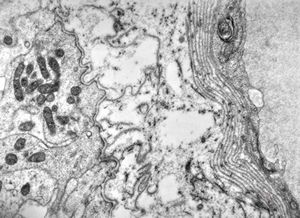

F,49y. | purulent meningitis- meningococcal v.s.

F,49y. | purulent meningitis- meningococcal v.s.

F,49y. | purulent meningitis- meningococcal v.s.